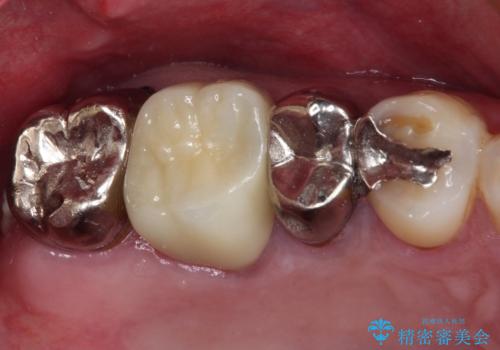

以前治療した歯が続々とむし歯に 全顎むし歯治療